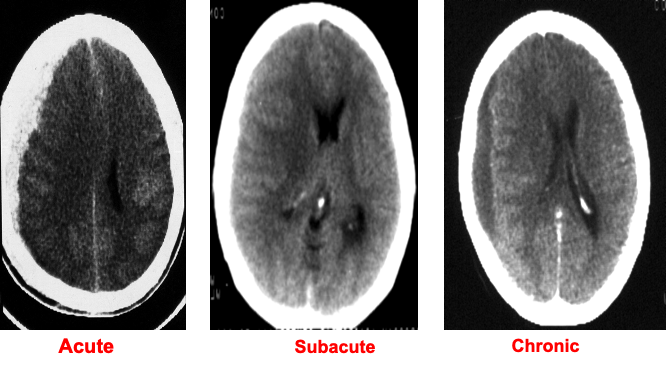

- Can be acute , subacute or chronic.

- Radiodensity of the lesion depends on the length of time since the inciting event:

- Acute SDH: hyperdense

- Subacute SDH: isodense

- Chronic SDH: hypodense